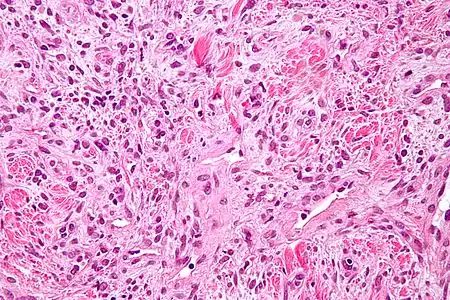

Les tumeurs fibreuses solitaires sont constituées de cellules mésenchymateuses, de différenciation fibroblastique[6]. Elles sont ovoïdes ou fusiformes. Leur cytoplasme est riche en collagène[3]. L'architecture tissulaire est hétérogène, supportée par un tissu conjonctif collagénique et alterne entre des zones bien fournies en cellules et des zones plus pauvres, où l'espace intercellulaire est plus riche en acide hyaluronique[3].

L'immunohistochimie retrouve l'antigène CD34 dans 80 % des cas[30], ce qui permet de différencier les tumeurs fibreuses solitaires des mésothéliomes[3]. Les tumeurs expriment également la vimentine, mais aucune des cytokératines[30].

Aspect en microscopie optique (coloration H&E).

Il existe quelques variantes histologiques. Les tumeurs fibreuses solitaires dites « anaplasiques » ou « dédifférenciées » sont de moins bon pronostic et peuvent prendre l'aspect d'un sarcome pléomorphe. Les variantes myxoïdes et lipidiques ne modifient en revanche pas le pronostic[48]. Les différents types de fusion entre les gènes NAB2 et STAT6 pourraient être à l'origine de ces variantes histologiques[49].